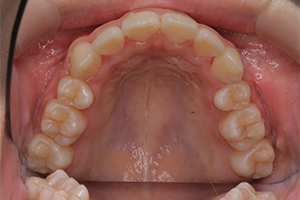

矯正治療のCASE 04

Before

After

-

- 主訴

- 歯並びがガタガタしていて清掃しにくい

- 治療内容

- ラビアル矯正(表側)

抜歯あり

- 治療費用

- 88万円~(税込)

- 治療期間

- 20か月

【リスク・副作用】

歯の痛み、口内炎、歯磨きがしにくいことによるむし歯や歯周病のリスク、歯根吸収や歯の変色、後戻りなどの副作用があります。